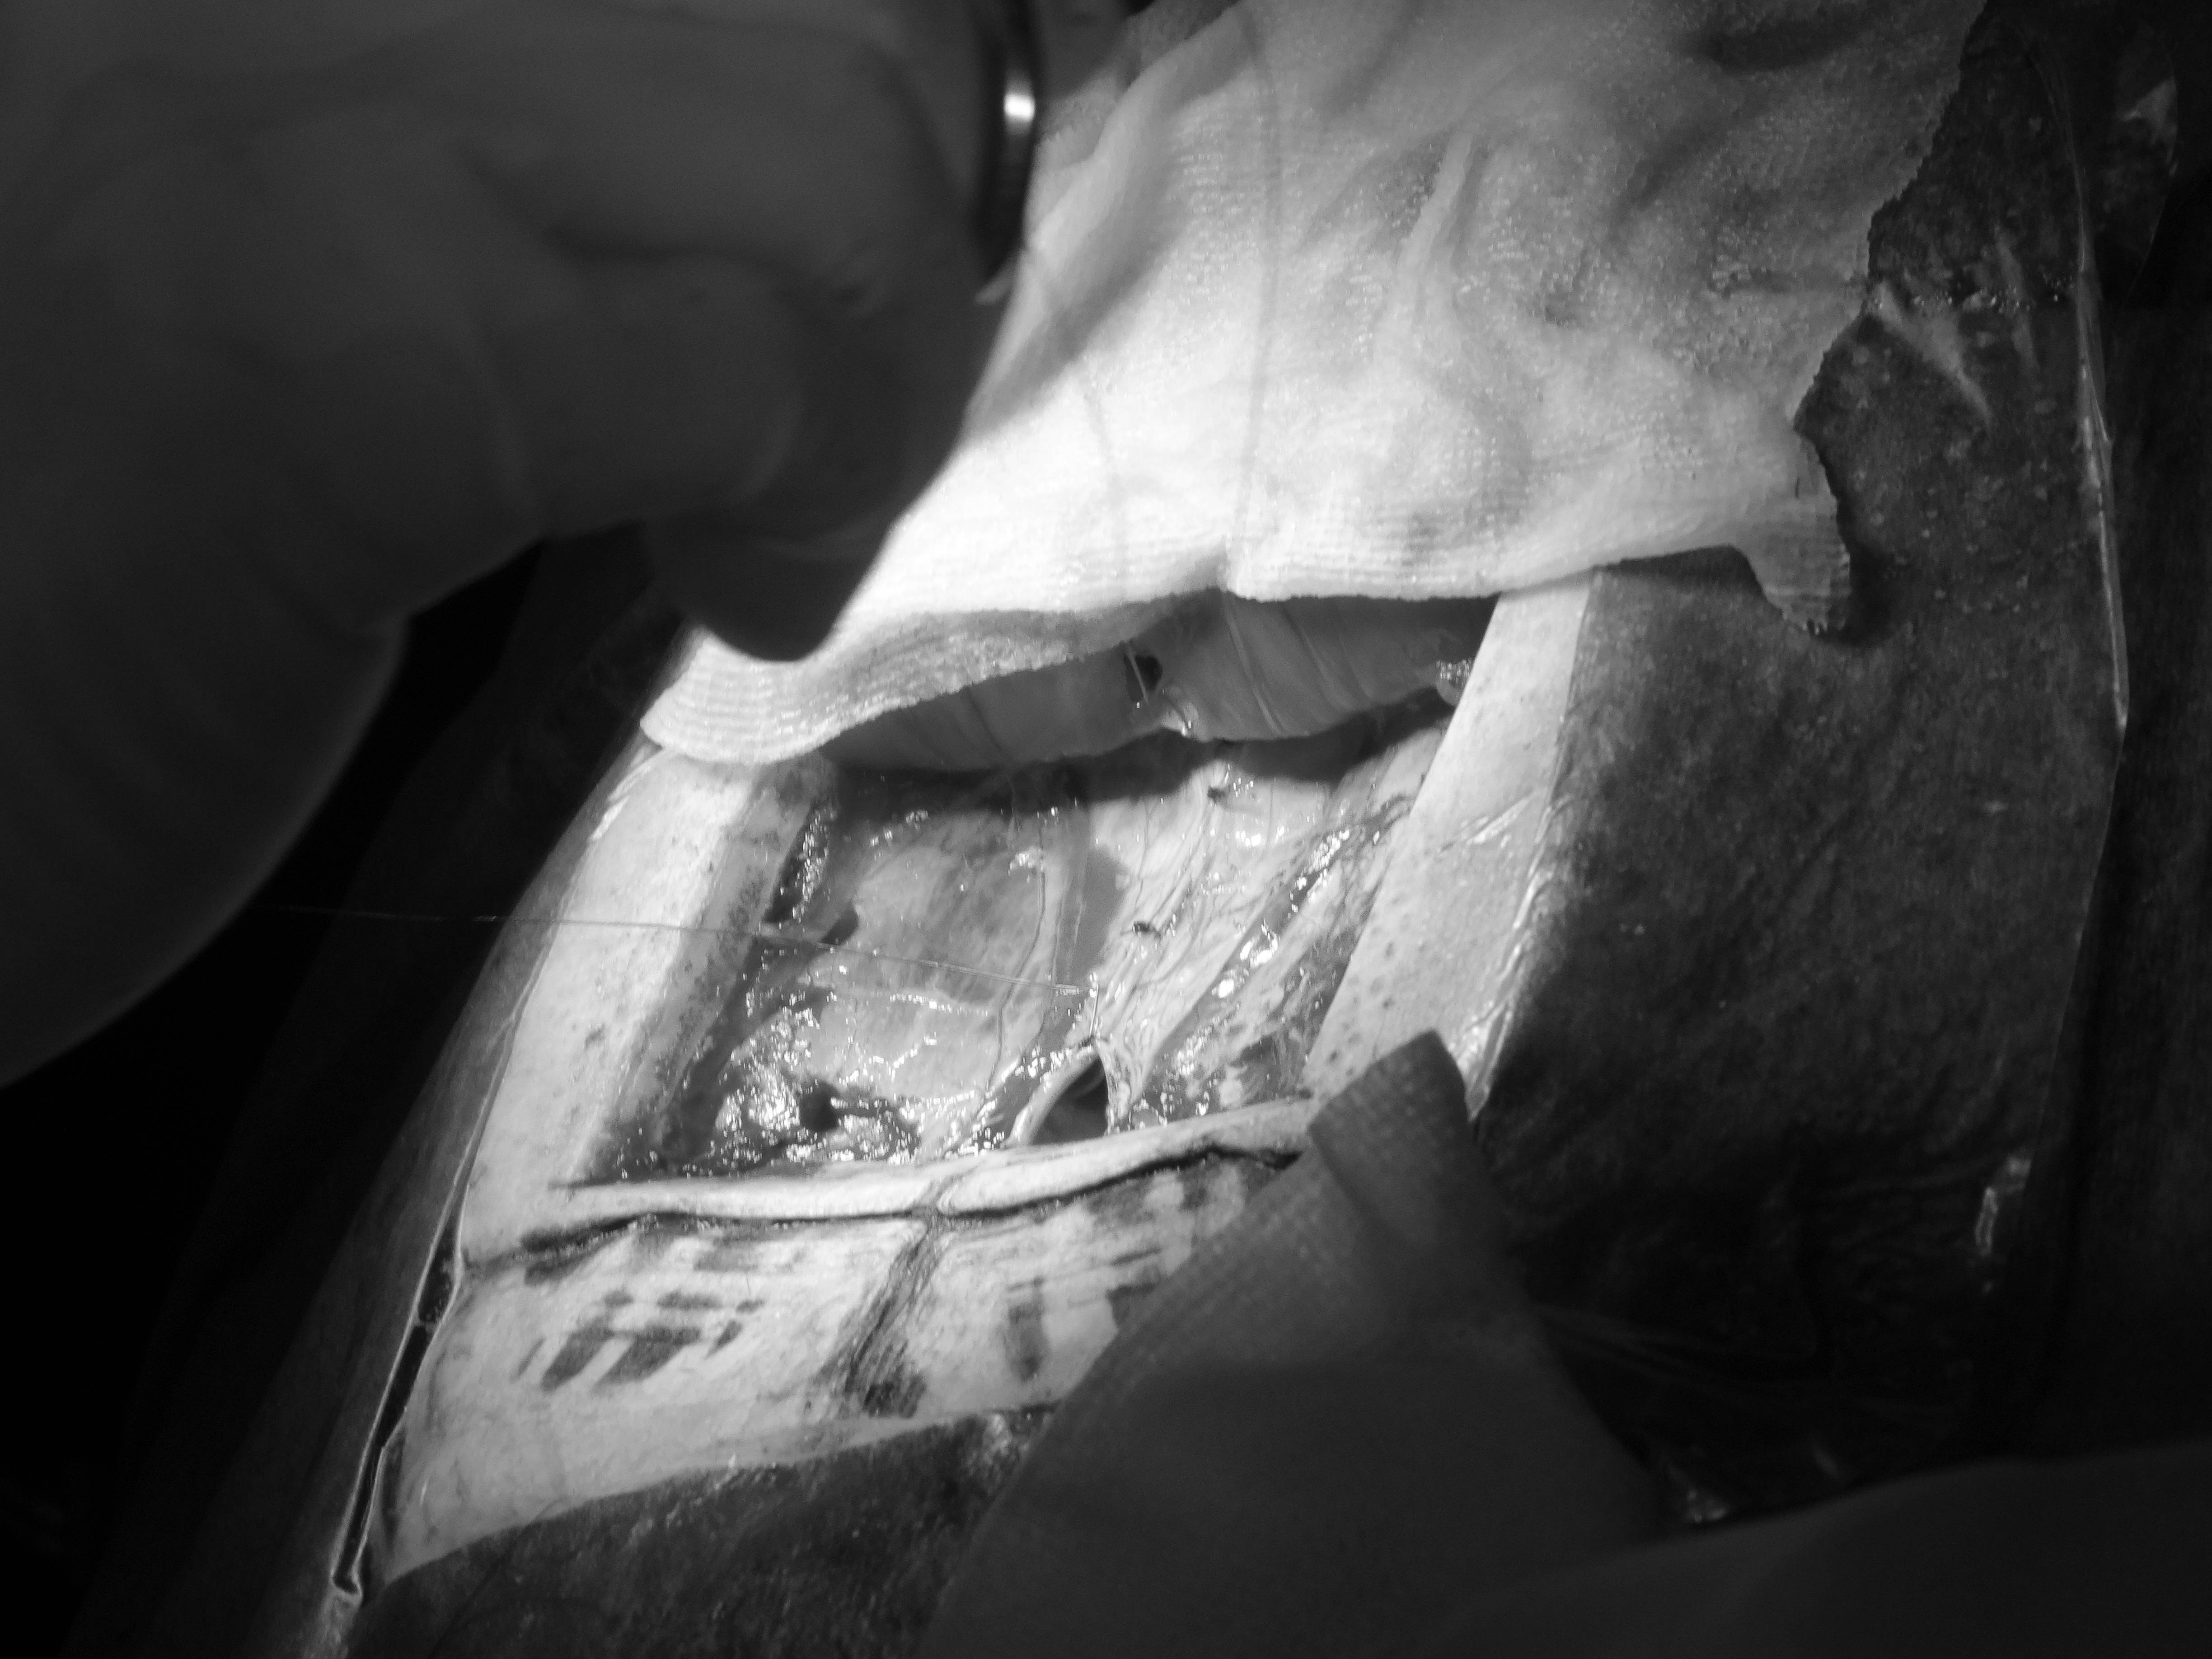

手術といっても、カメには硬い甲羅があるので、まずそれを切らないといけません。医療用の電動ノコギリのような器械を使って切開します。

そのあとは哺乳類や鳥類と同じように、腹膜を切開して、卵巣と卵管を切除しました。

なかなか産まれなかった卵は、卵管の外にある状態(卵墜といいます)だったので、取り出しました。

一部は膀胱にくっついていたので、その部分の膀胱を切除し縫合しました。

すべて終わると腹膜を元通り閉じて縫合し、甲羅も閉じます。

白い円盤は接着剤として使用している補修剤(エポキシパテ®)です。

さてこの写真をよく見ると、切開した線が二重にあるのがわかるでしょうか。

実はこのホシガメ、4年前にもやはり卵を産まなくて、一度開腹手術をしているのです。そのときは、卵管から卵を取り出すだけで、手術を終えました。そのときに切開したのが内側の黒い線です。